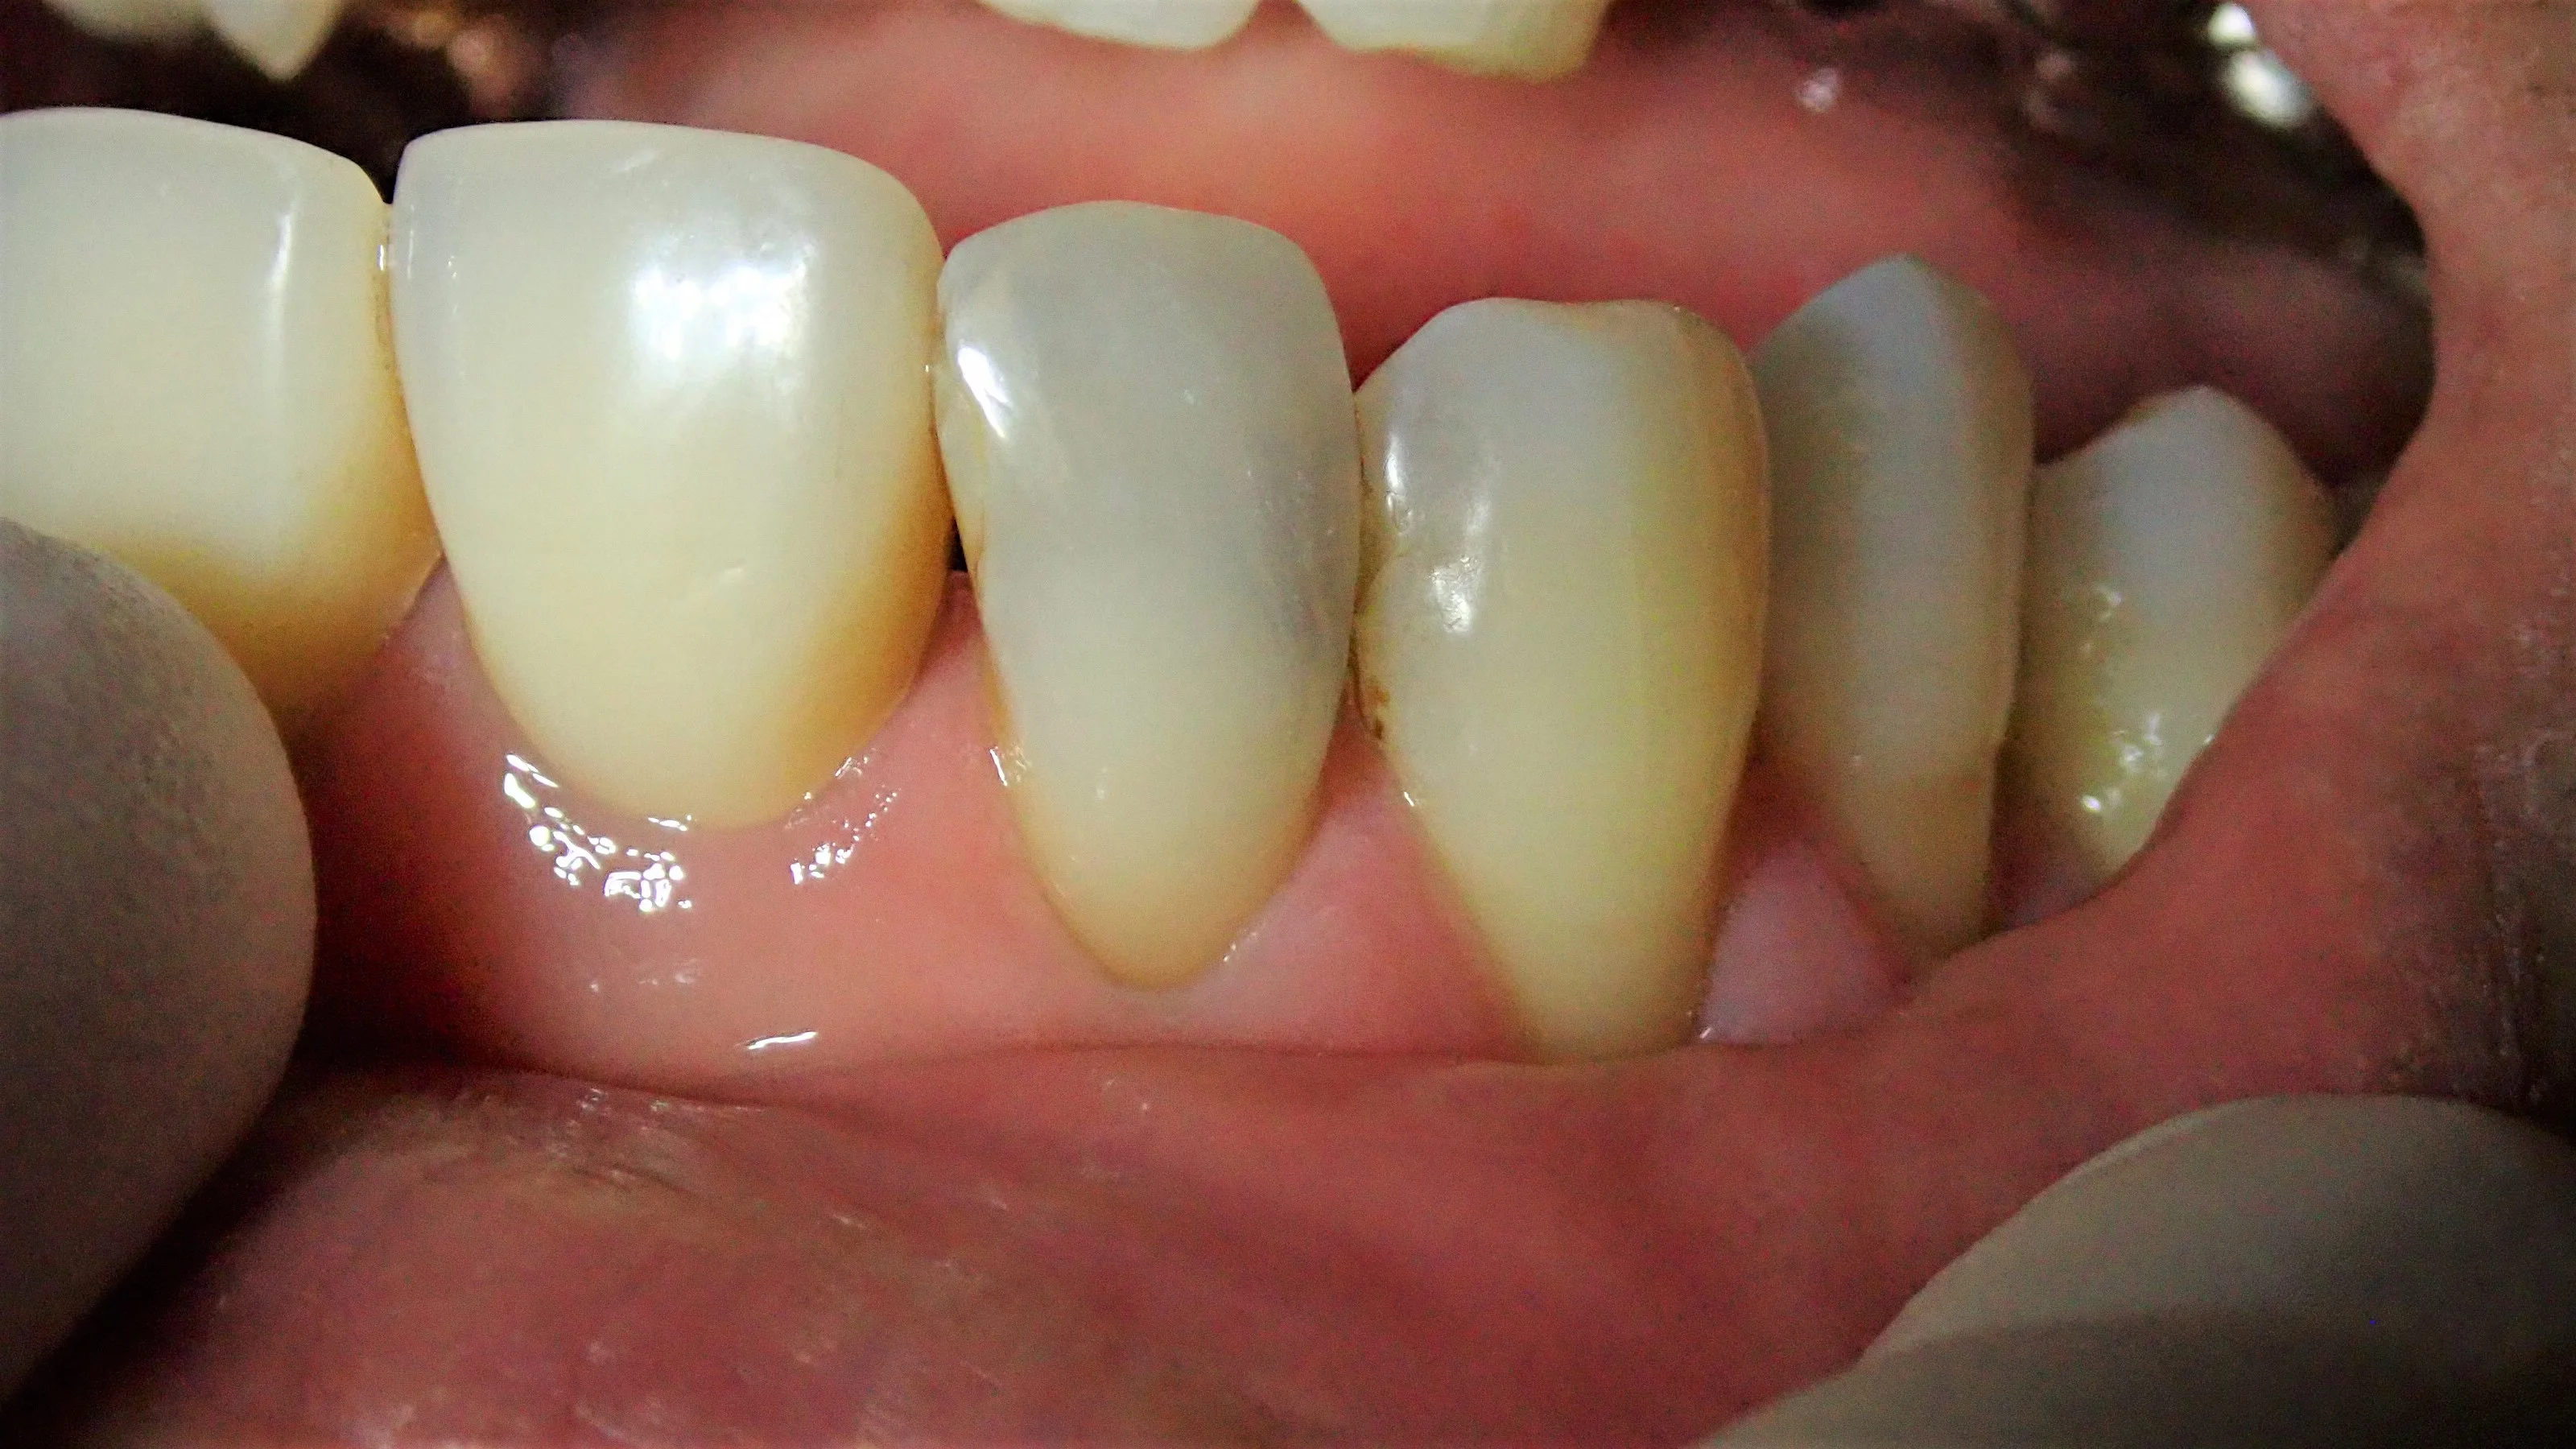

まずは術前の状態です。

歯の表側から見た状態です。

どこが虫歯か分かりますかね?

今回は結構色が透けているので、なんとなく虫歯になってるっぽいなと一般の方でも分かるかと思いますが・・・